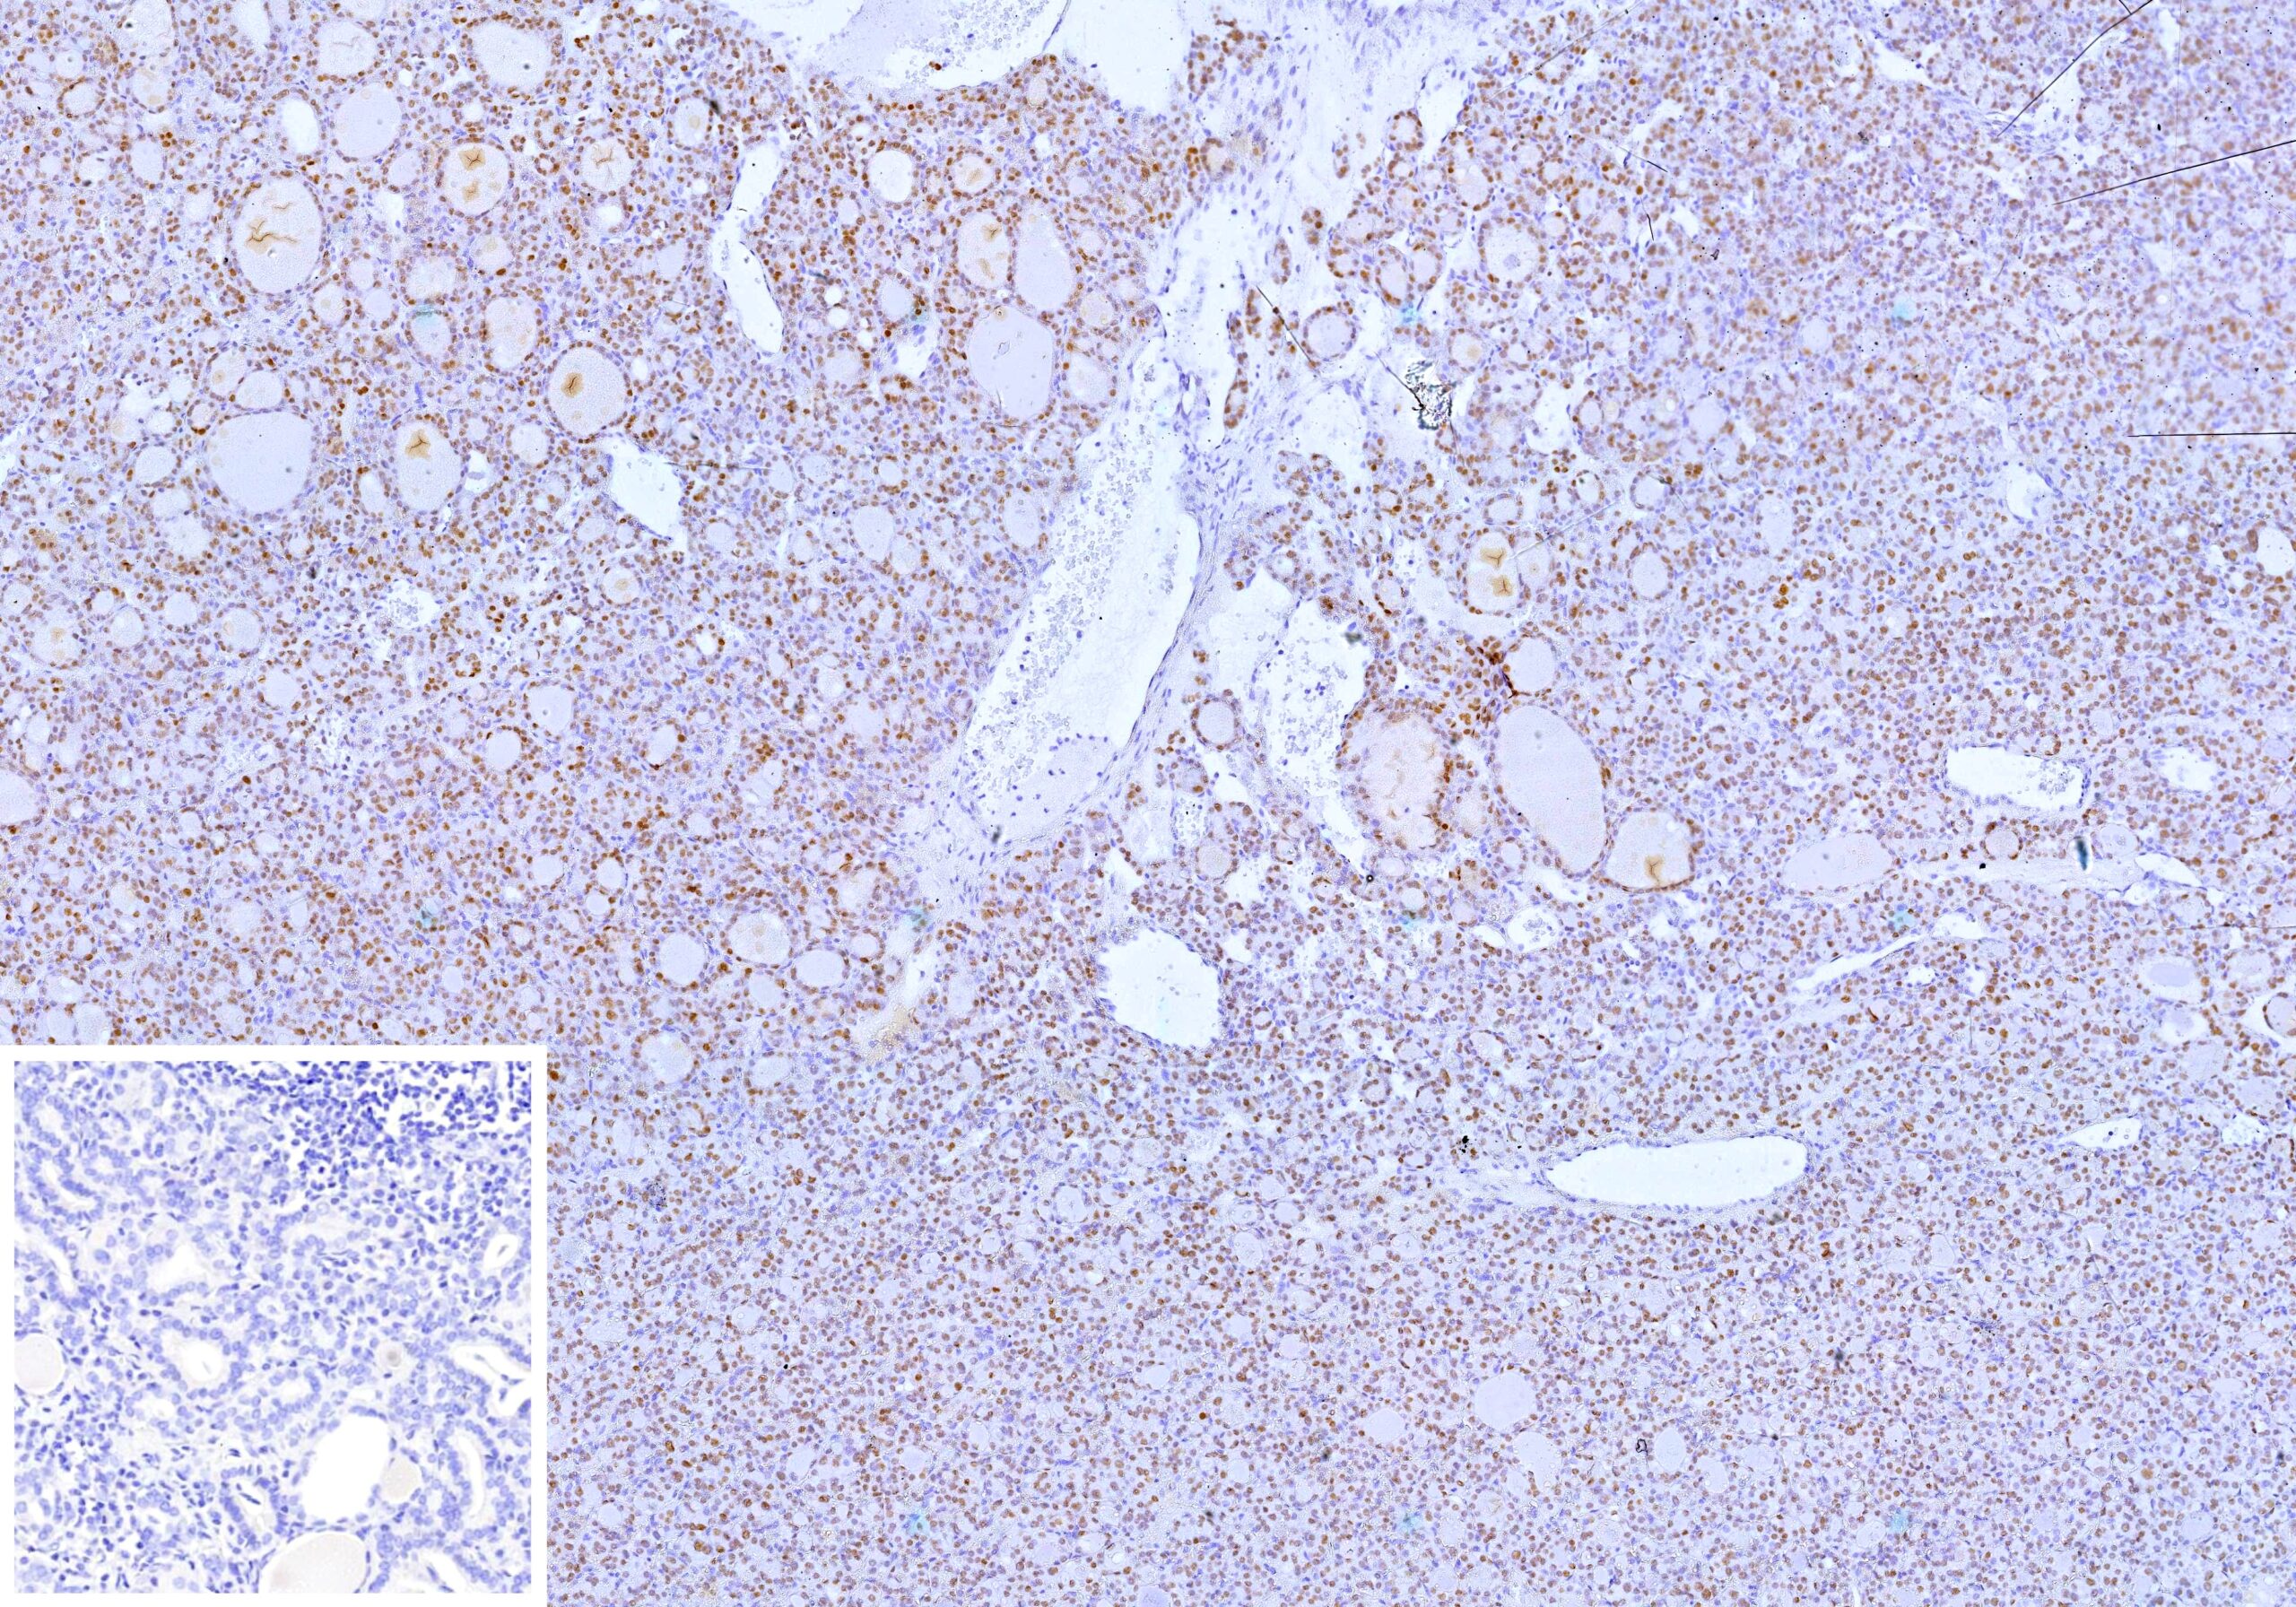

Recognizes a protein of 62kDa, identified as PAX8. It is a member of the paired box (PAX) family of transcription factors. This nuclear protein is involved in thyroid follicular cell development and expression of thyroid-specific genes. Mutations in this gene have been associated with thyroid dysgenesis, thyroid follicular carcinomas, and atypical thyroid adenomas. PAX-8 is expressed in the thyroid (and associated carcinomas), non-ciliated mucosal cells of the fallopian tubes, and simple ovarian inclusion cysts, but not normal ovarian surface epithelial cells. PAX-8 is expressed in a high percentage of ovarian serous, endometrioid, and clear cell carcinomas, but only rarely in primary ovarian mucinous adenocarcinomas. PAX-8 expression is reported in renal tubules as well as renal cell carcinoma, nephroblastoma, and seminoma. PAX-8 antibody may be used as an additional immunohistochemical marker for renal epithelial tumors.

HeLa or Raji cells. Human renal cell carcinoma (RCC) or ovarian serous carcinoma.